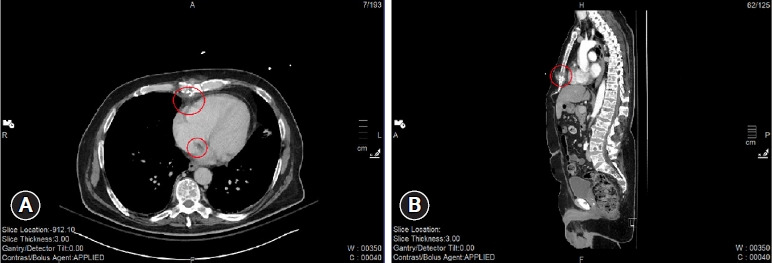

子弹栓塞是枪伤的一种潜在并发症,尤其是在使用低速导弹时。这是因为低速子弹穿过组织时,弹道会明显变慢。可能会出现一种不寻常的飞行形式,即子弹进入血管,但没有足够的动能造成贯穿伤,导致子弹留在血管内。一旦进入血管,子弹就会转移到身体的不同部位,可能会引起缺血、血栓栓塞或感染等并发症。子弹栓塞的处理方法因病例而异,因为每位患者都有独特的身体习惯,这可能导致子弹栓塞的轨迹和目的地出现无限可能。周围血管或组织可能受到额外损伤,子弹也可能栓塞到身体的关键部位。我们在此介绍一名 72 岁男性的病例,他的胸部被一颗低速子弹自残,子弹穿透了心脏右心房。子弹穿过右心房进入静脉血管,进入下腔静脉,最终落在右髂内静脉。经过初步检查和抢救,他拒绝接受进一步的干预和治疗。

Bullet embolism is a potential complication of a gunshot wound, especially with a low-velocity missile. This is because the trajectory of the low-velocity bullet can be significantly slowed as it passes through tissue. An unusual form of travel can occur in which the bullet enters the vasculature but does not have enough kinetic energy to create a through-and-through wound, leading it to remain inside the vasculature. Once inside the vasculature, the bullet could migrate to different parts of the body, potentially causing complications such as ischemia, becoming a source of thromboembolism, or functioning as a nidus for infection. The management of a bullet embolism varies from case to case, as each patient with this issue has a unique body habitus that can result in infinite possibilities of the trajectory and destination of the bullet embolus. Additional damage to surrounding vasculature or tissue can occur, as well as embolization of the bullet to critical areas of the body. Here we present the case of a 72-year-old man who had a self-inflicted gunshot wound to the chest with a low-velocity bullet, which penetrated the right atrium of the heart. It traveled into the venous vasculature through the right atrium, into the inferior vena cava, and eventually settled in the right internal iliac vein. He refused further intervention and management after initial workup and resuscitation.